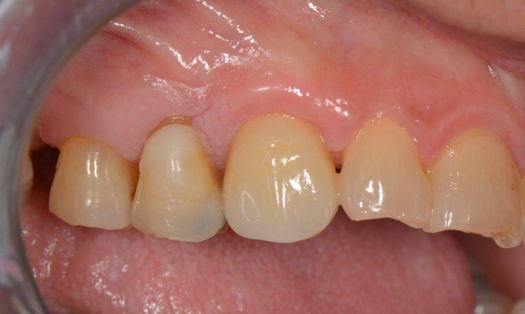

Fig 6. After splint removal (12 weeks postoperatively).

Figure 6

Fig 7. 12 weeks postoperatively.

Figure 7

Figure 3 through Figure 5 show the fitting of a one-piece multiple splint using a light-cured acrylic, along with flowable composite to adhere the splint to the three ceramic dental implants. The splint was to remain out of occlusion, without any occlusal forces for the 12-week osseointegration period. The patient was instructed to chew on the other side of her mouth for the 12 weeks before returning to the dental practice for simple removal of the splint. Removal of the splint revealed optimum results. The soft tissues were pink, with keratinized gingival margins completely surrounding the ceramic implants and consistent with what most dentists observe with the periodontium around periodontally healthy natural teeth (Figure 6 and Figure 7).